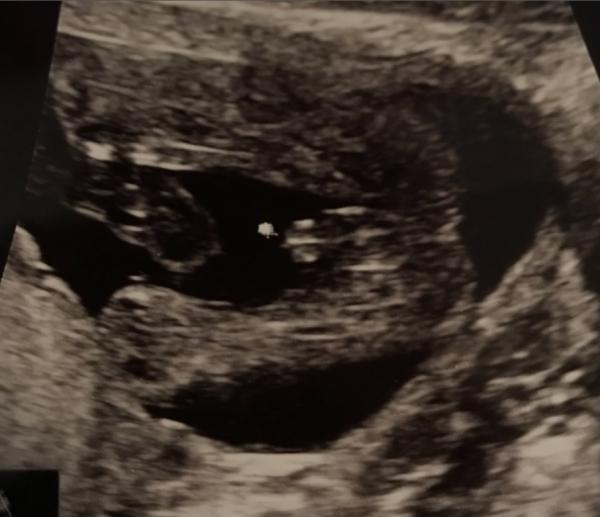

Hallo an alle Schwangeren die villeicht auch gerade vor ihren ulltraschallbildern sitzen und sich ihren Kopf zerbrechen😅 Ich bin aktuell in der 18ssw bei 17+0 hatte ich einen ulltraschall wo mein Gynäkologe auch super zwischen die Beine vom Baby schallen konnte. Erst sagte er das  ist ein Mädchen dann kurz Stille 🤫 " Ich bin mir doch nicht so ganz sicher" na toll 😅 da sitze ich nun mit einem Bild von Geschlecht und Rätsel zusammen mit meinem Mann. Ich habe bereits drei Kinder allerdings passt kein outing Bild zu dem hier. Bei meinem Sohn war es sowas von eindeutig und bei den beiden Mädels auch. Ich muss sagen das ich bei den andren Kindern schon in der 22 ssw war als ich die outings bekommen habe. Plus nipt test den habe ich in dieser ssw nicht gemacht. Hat jemand ähnliche Bilder oder Erfahrungen und würde villeicht ein Tipp abgeben. Ich freue mich über alle Meinungen ☺️

Bild zu Mädchen oder Junge? Was meint ihr 😀 - Schwanger - wer noch? Rund um die Schwangerschaft

Ich würde tatsächlich sagen, dass es für mich nach einem Babyboy aussieht!  Die meisten verwechseln die drei Linien. Hab mal zwei Bilder im Internet rausgesucht die beide um ca. 20te Woche gewesen sind.  Beim ersten Bild packe ich mal den Jungen rein, beim zweiten das Mädchen. Beide haben drei Linien aber man sieht den kleinen Jungen. Beim Mädchen die Schamlippen Aufteilung.  Bei uns sah es aber echt ungelogen aus wie beim Mädchen. Kann mir bis heute keiner erklären, warum es so war 😄  Aber gut, ab der 25ten woche war aber sofort auf einen Blick zu erkennen was der kleine so zwischen den Beinen hat 😄😄😄